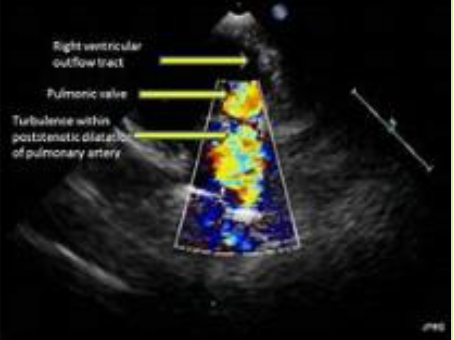

What are the echo findings?

A

• thickening if the PV leaflets with systolic doming

• RV hypertrophy due to RV pressure overload = increased afterload

• flattening if the IVS due to the RV pressure overload *D shaped LV (can be visualized in PSAX)

• RA enlargement

• RV failure in the later stages of PS

• post-stenotic dilatation of the MPA due to the high velocity PS jet striking the PA wall *similar to AS

Explain how to assess with Doppler

similar to AS, assess:

• peak velocity

• max & mean PG

• PVA

via the continuity equation

• CW focus in the PV; acquire the PV peak velocity & the VTI

• PW gate in the RVOT; acquire the RVOT peak velocity & VTI

*For a quick PG, utilize the modified Bernouli’s equation: PG = 4V2